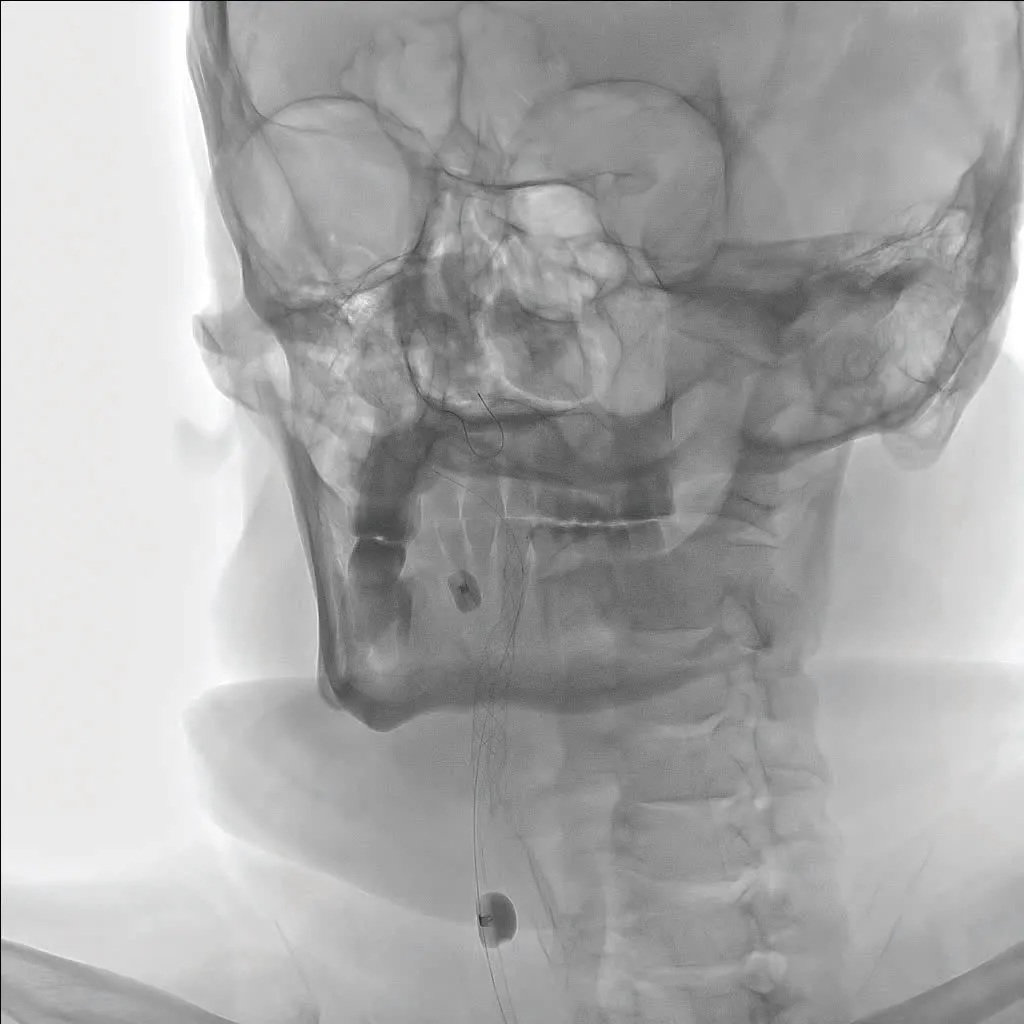

A pigtail catheter was positioned in the aortic arch and an arch aortogram was obtained, confirming the presence of a type I aortic arch without significant calcification. Significant tortuosity was noted in the innominate artery (Figure 2). The catheter was then switched out for a 5-F vertebral shaped catheter that was used to cannulate the left CCA, and carotid and cerebral angiograms were obtained. These showed no significant stenosis of the left carotid system, with cerebral angiograms showing antegrade filling of the left anterior artery and middle cerebral artery (MCA), as well as contralateral filling of the right anterior cerebral artery (ACA) and MCA (Figure 3).

Figure 2. Significant tortuosity noted in the innominate artery.

Figure 3. Cerebral angiogram showing antegrade filling of the left anterior artery and MCA and contralateral filling of the right ACA and MCA.

The vertebral catheter was then used to cannulate the innominate artery and advanced over a 0.038-inch Glidewire to the right CCA. Subsequent carotid and cerebral angiography showed no significant stenosis of the CCA and a widely patent external carotid artery (ECA). A critical subtotal occlusion of the proximal ICA (Figure 4) was noted, with sluggish TICI (thrombolysis in cerebral infarction) 1 to 2 flow in the distal ICA into the MCA; the ACA was not filling antegrade (Figure 5).

Figure 4. Critical subtotal occlusion of the proximal ICA.

Figure 5. Sluggish TICI 1 to 2 flow in the distal ICA into the MCA, with an ACA not filling antegrade.